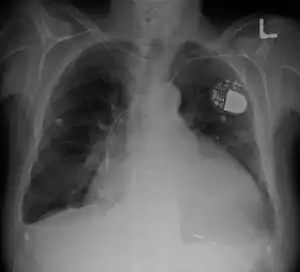

| Cardiomegaly on chest X-ray with a pacemaker | |

- Chest X-Ray: X-ray images help see the condition of the lungs and heart. If the heart is enlarged on an X-ray, other tests will usually be needed to find the cause. A useful measurement on X-ray is the cardio-thoracic ratio, which is the transverse diameter of the heart, compared with that of the thoracic cage."[19] These diameters are taken from PA chest x-rays using the widest point of the chest and measuring as far as the lung pleura, not the lateral skin margins. If the cardiac thoracic ratio is greater than 50%, pathology is suspected, assuming the x-ray has been taken correctly.[20] The measurement was first proposed in 1919 to screen military recruits. A newer approach to using these x-rays for evaluating heart health takes the ratio of heart area to chest area and has been called the two-dimensional cardiothoracic ratio.[21]

- Pacemaker: Coordinates the contractions between the left and right ventricle. In people who may be at risk of serious arrhythmias, drug therapy or an implantable cardioverter-defibrillator (ICD) may be used.